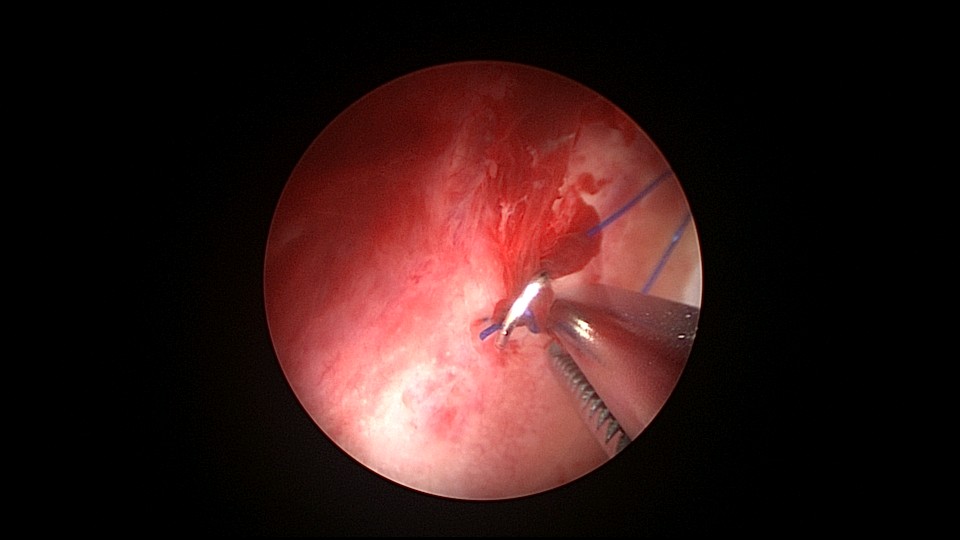

患者46岁,G2P2,顺产2次。因子宫腺肌症,严重痛经,8年前在江苏某医院放置曼月乐环,1+月后环脱落,未再继续治疗腺肌症,忍受了近7年痛经折磨。1+年前在外院再次放置曼月乐环,病人讲述手术医生做了环固定,最近月经量增多,痛经恢复至放环前,安环医院B超提示子宫后位,环已脱落,子宫7.4cm*7.4cm*8.4cm大小,朋友介绍到我院做曼月乐固定。宫腔镜见子宫后倾后屈位,宫深8.5cm,无法看到两侧宫角及子宫后壁,放弃缝合固定,用挂钩固定曼月乐环于宫底,先将不锈钢挂钩插入宫底肌层,4-0不可吸收线在曼月乐横臂中间套扎形成线圈,将曼月乐置入宫腔,异物钳夹持线圈挂到不锈钢挂钩里,原位固定曼月乐,退出宫腔镜,结束手术。术后多次复查B超,曼月乐位置正常,环顶端距宫底2.0cm。